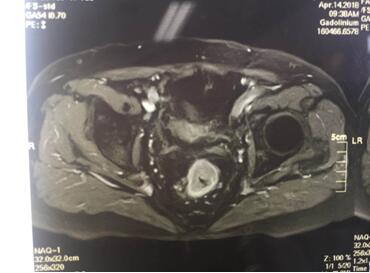

入院后譚曙光主任帶領賀賽奇副主任、周高副主任醫(yī)師及周平主治醫(yī)師等科室業(yè)務骨干為汪老制定詳細診療計劃。術(shù)前盆腔MRI及腸鏡、病理診斷考慮低位直腸腺癌(T3aN0M0)。鑒于汪老年老體弱,病變位置低,基礎疾病多,耐受力較差,譚主任及其手術(shù)團隊精益求精,不斷完善診療措施,術(shù)前采取MDT(多學科合作)模式,于4月18日在全麻腹腔鏡下行直腸癌根治術(shù)+D3淋巴結(jié)清掃術(shù)+粘連松解,手術(shù)順利,術(shù)中徹底松解腹腔內(nèi)粘連,標準的TME(直腸全系膜切除)及D3淋巴結(jié)清掃,腹腔鏡下吻合口加固縫合,手術(shù)出血僅30ml,在原有的手術(shù)切口處取出手術(shù)標本。